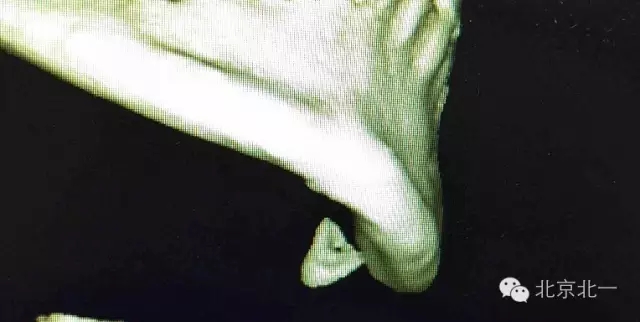

圖二:CBCT掃描重建清晰看到舌側(cè)骨板骨折,牙根位于舌側(cè)。而不是進入下牙槽神經(jīng)管。